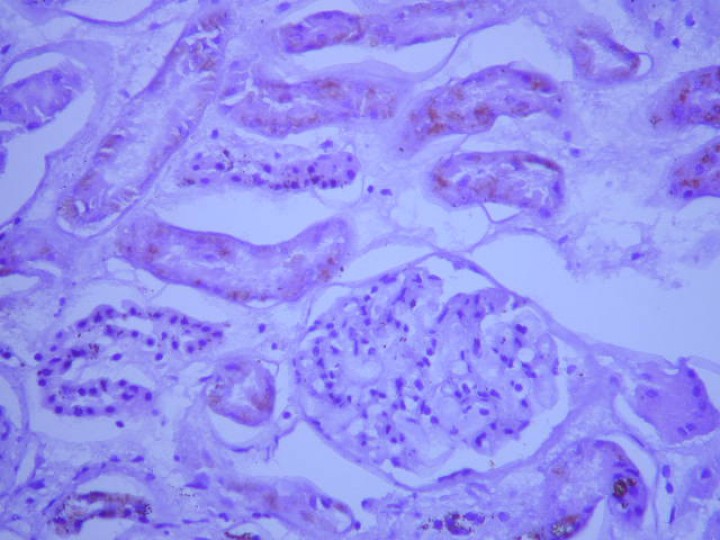

Hurón hembra de dos años de edad, no esterilizada, que presentaba debilidad generalizada, esplenomegalia, linfadenomegalia abdominal y nefromegalia unilateral (Figs. 3 y 4). La analítica sanguínea mostraba pancitopenia, hipoalbuminemia e hiperglobulinemia. El proteinograma reveló un aumento generalizado de globulinas con una marcada gammapatía policlonal (Tabla 3).

<p>Nefritis y nefromegalia en un paciente con coronavirus sistémico (sección renal).</p>

Figura 3

Nefritis y nefromegalia en un paciente con coronavirus sistémico (sección renal).

<p>Imagen histopatológica (nefritis piogranulomatosa y linfoplasmocitaria con glomerulonefritis membranosa asociada). Tinción hematoxilina-eosina, 400 aumentos.</p>

Imagen histopatológica (nefritis piogranulomatosa y linfoplasmocitaria con glomerulonefritis membranosa asociada). Tinción hematoxilina-eosina, 400 aumentos.